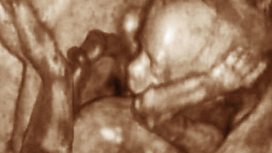

Spina bifida baby operated on whilst still in mother's womb

We discuss this remarkable surgical procedure.